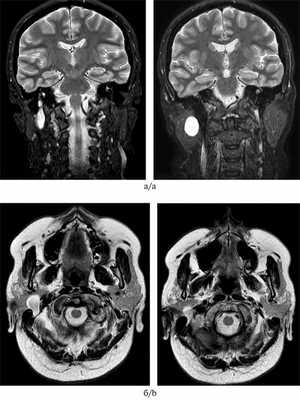

В ЦНИИС и ЧЛХ обратилась пациентка О., 50 лет, с жалобами на наличие бессимптомного, медленно растущего опухолевидного образования в области правой околоушной слюнной железы без клинических признаков вовлечения в процесс лицевого нерва, таких как слабость мимической мускулатуры или непроизвольные ее сокращения. Опухоль была случайно выявлена при проведении магнитно-резонансной томографии (МРТ) головного мозга в связи с поиском причин систематических приступов головной боли у пациентки. Во время осмотра при пальпации в зачелюстной области определялось безболезненное, подвижное образование мягкоэластической консистенции, не спаянное с окружающими тканями, около 2,5 см в диаметре в медиальной части правой околоушной слюнной железы. Пациентка наблюдалась в ЦНИИС и ЧЛХ на протяжении нескольких лет. Ежегодно выполнялось ультразвуковое исследование (УЗИ) околоушной области справа (рис. 1). Рис. 1. УЗИ околоушной области пациентки О., 50 лет. а — УЗИ 2016 г. В глубокой части правой околоушной железы на глубине от 15 мм наблюдается гипоэхогенное образование с четкими контурами, без признаков наличия кровотока, 22×14×20 мм. При компрессии образование деформируется незначительно; б — УЗИ 2017 г. Отмечено увеличение образования (27×17×22 мм) без изменения признаков. Рост образования составил около 5,0 мм за 2 года.

Учитывая медленный рост образования и его бессимптомное течение, с пациенткой обсуждались выжидательная тактика и продолжение динамического наблюдения. Однако в связи с нарастающей тревогой и онкологической настороженностью у пациентки, а также настоятельной ее просьбой удалить образование было принято решение о проведении хирургического вмешательства. На этапе предоперационной подготовки с диагностической целью пациентке были выполнены МРТ (рис. 2), Рис. 2. МРТ (1,5 Тл) больной О., 50 лет. Исследуемая область: околоушные слюнные железы. Контрастное усиление не применялось (2018 г.). а — МРТ в режиме Сoronal, Т2-ВИ. В области правой околоушной железы — гомогенное, гиперинтенсивное образование; б — МРТ, Т2-ВИ FS Axial. Имеется гиперинтенсивный сигнал с периферии образования, гипоинтенсивная центральная зона, так называемая target sign (знак мишени). На МРТ в режиме Т2 образование имеет каплевидную (гантелеобразную) форму, ориентировано по направлению к фаллопиевому каналу. тонкоигольная аспирационная биопсия образования и цитологическое исследование. По результатам каждого из проведенных методов, включая цитологическое исследование, был установлен диагноз: плеоморфная аденома околоушной слюнной железы справа.